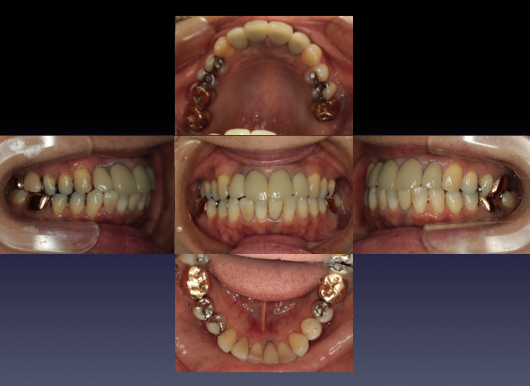

症例⑤

上左右の奥歯を失ってしまったため、保険の入れ歯を入れたが、違和感が強く、しっかり噛むことができないため、インプラントを併用した入れ歯を作ることで違和感なく、しっかり噛むことができるようになった。 また通常の入れ歯は、はずれないようにするため金属のバネを歯に引っ掛けるため見た目も悪いが、インプラントによって固定されているためバネもなく、見た目も非常に良いものとなっている。

術前